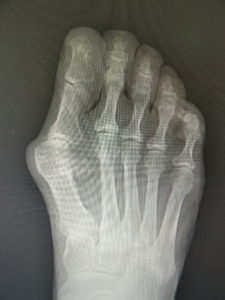

おおむね、外反角が30度以上になると、保存治療はもはやあまり有効ではありません。症状が強く、患者さんと良く吟味の上、希望されれば手術へと進みます。他に根治療法はないが、手術なら根治できます(図5)。ただMP関節の変性性変化があると、痛みや拘縮が残ることがあります。

(図5)

手術前 手術後4年

(図6)

手術前 手術後

(図7)

この手術は、人工関節手術などと異なり、何も人工物を体内に残さない、優秀な手術です。罹患以前の状態に戻るという意味で、本来的な根治術といえるでしょう。変形が治るので、靴が履きやすくなり、しっかりリハビリしてMP関節の動きがよくなれば、運動も自由に行えるようになります。

真田理事長による手術の様子。外反母趾|症例 (左から 手術前、手術後、ワイヤ抜去後)